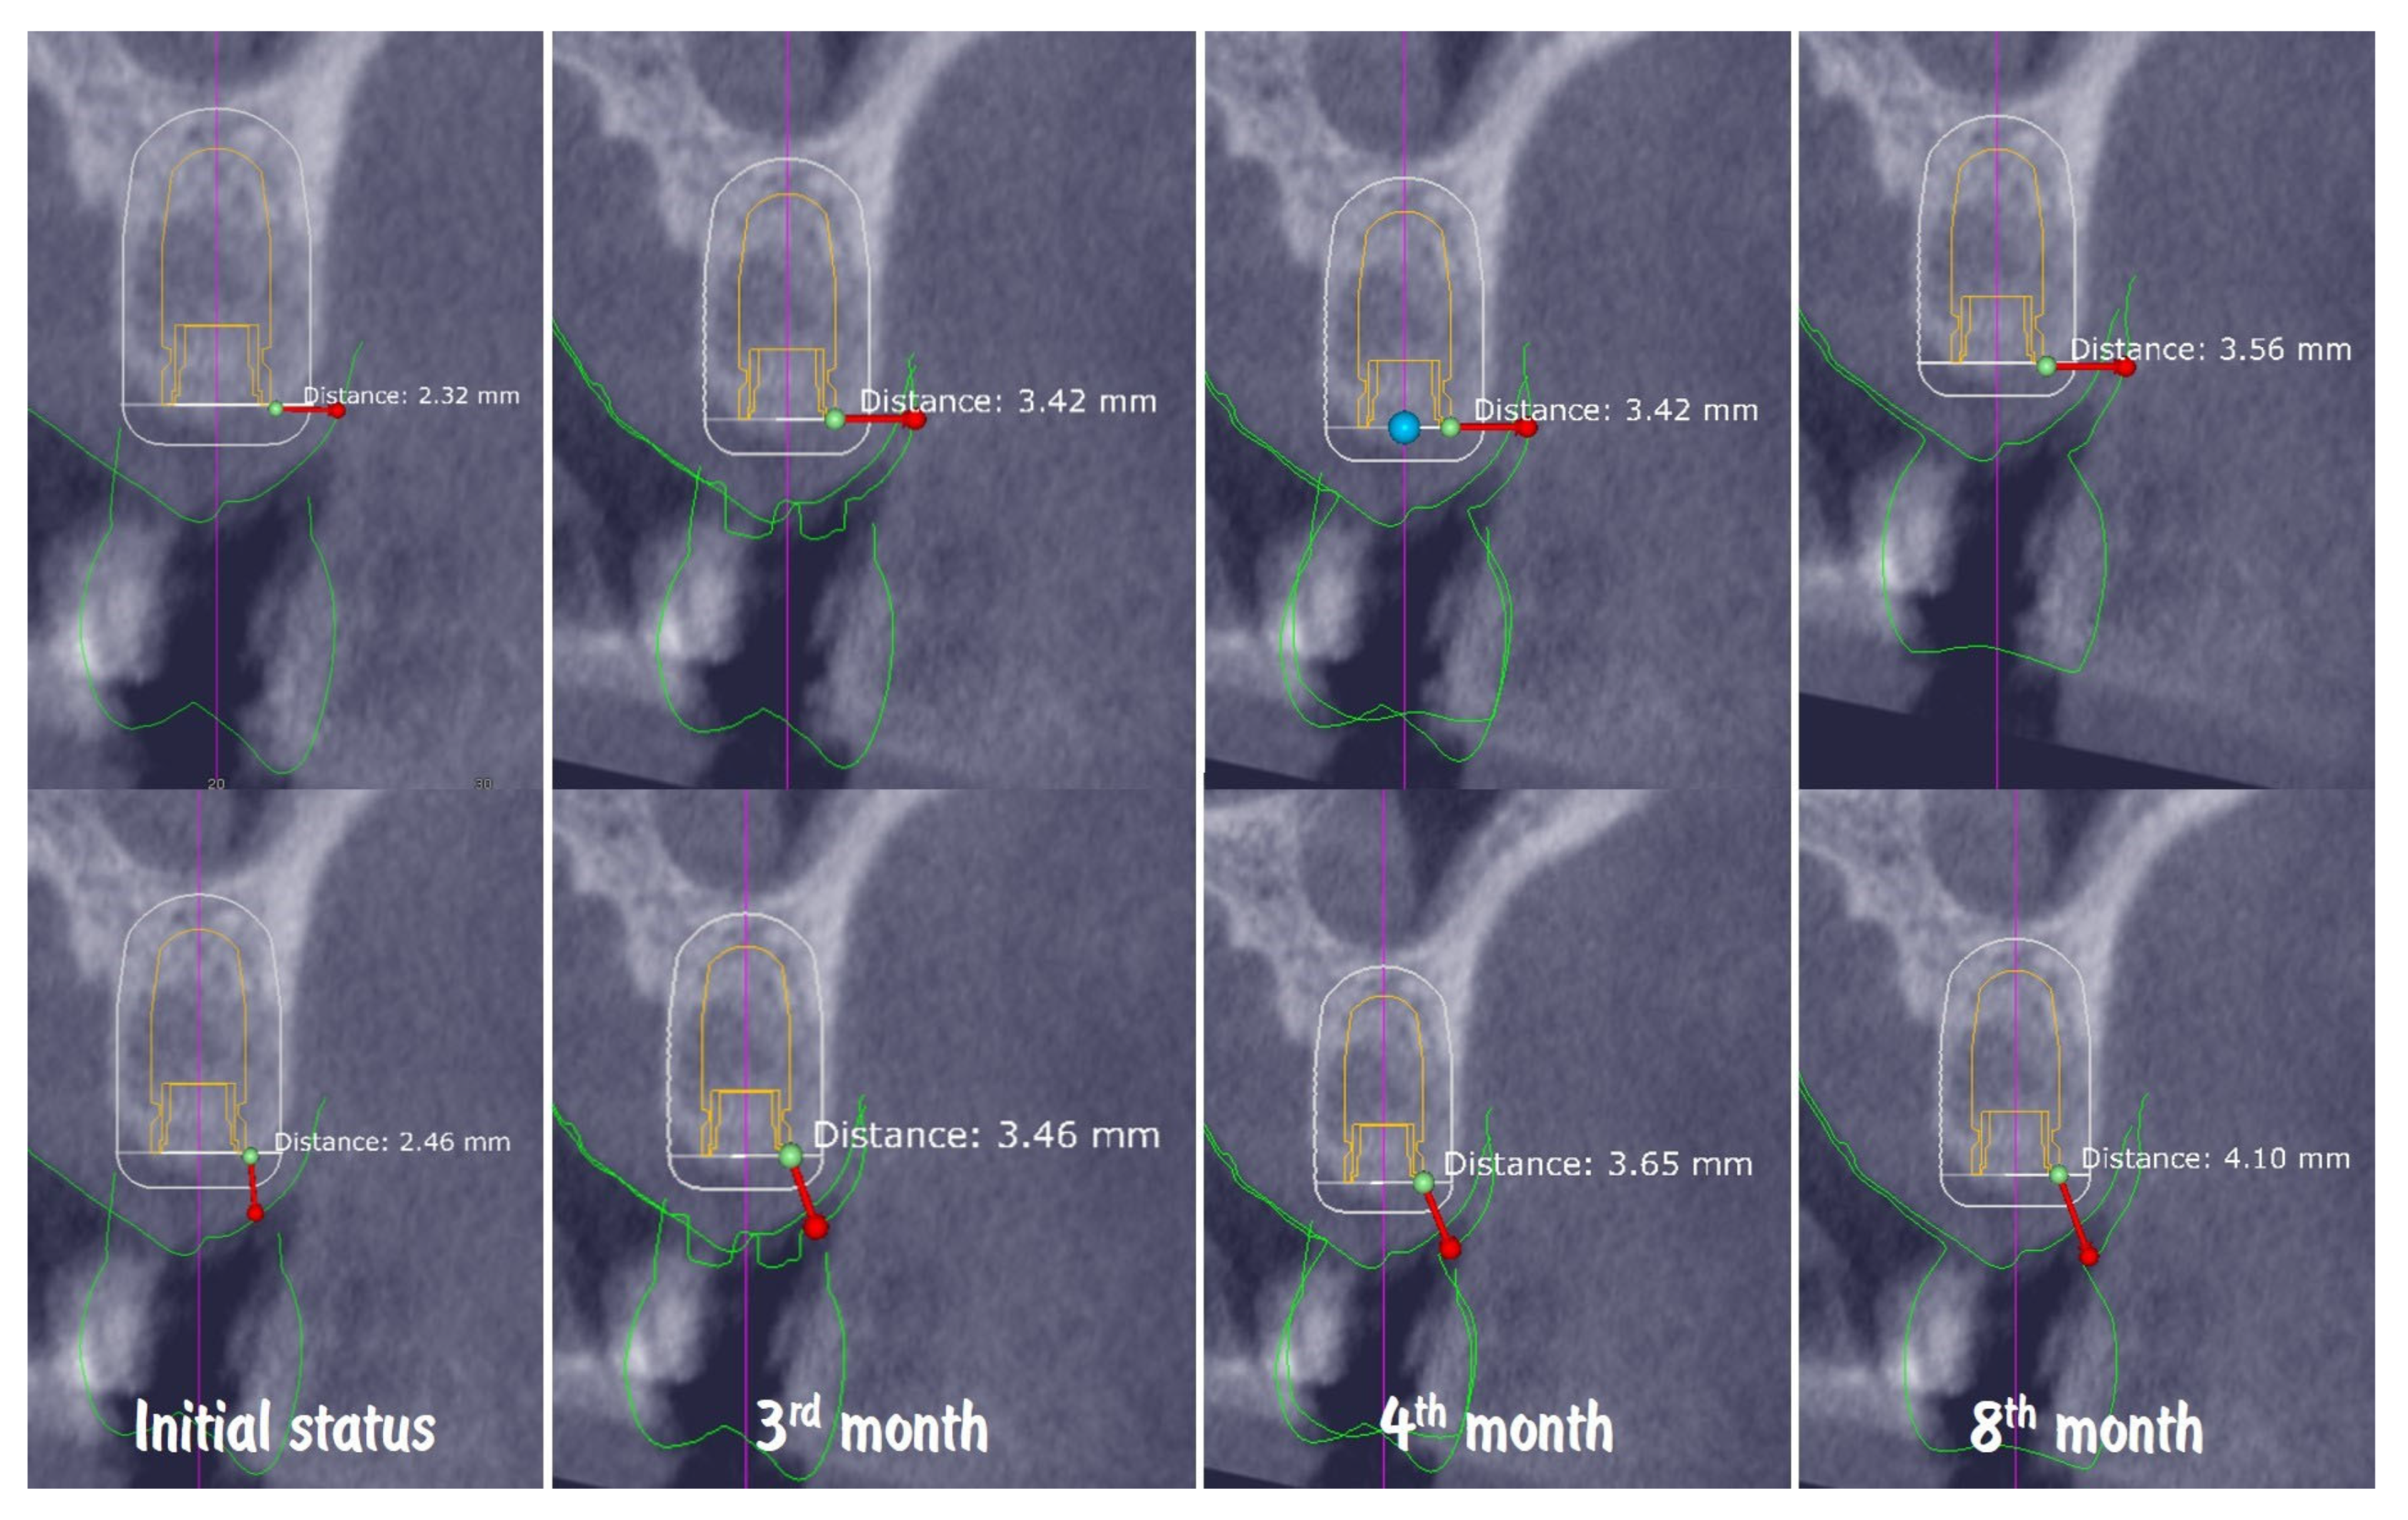

Figure 20 shows the dynamic of soft tissue maturation and development. The combination from soft tissue augmentation procedure with the modified roll flap and soft tissue conditioning with the temporary crown led to complete resolution of the horizontal defect of the alveolar crest and provided adequate soft tissue thickness for long-term stability of the implant-supported restoration.

Figure 20.

Dynamic of soft tissue maturation and development.

Digital volumetric analysis illustrates the stable increase in the peri-implant soft tissues over time, presented in (Figure 21). The buccal soft tissue dimensions increased from 2.3 mm horizontal thickness and 2.4 mm vertical thickness at baseline (Day 0) to 3.4 mm horizontal thickness and 3.4 mm vertical thickness at the 3rd month, showing approximately 1 mm thickness increase from the soft tissue augmentation procedure. One month after the connection of the temporary crown, the vertical thickness increased to 3.6 mm. At the time of the final crown placement, the horizontal thickness was 3.5 mm, and the vertical thickness was 4.10 mm, demonstrating the potential of the emergence profile of the crown to induce increase in the soft tissue thickness. The soft tissue thickness increase for the period of 8 months was 1.24 mm (53.45%) in horizontal dimension and 1.64 mm (66.67%) in vertical dimension.

Figure 21.

Digital volumetric analysis of the increase in the peri-implant soft tissues.